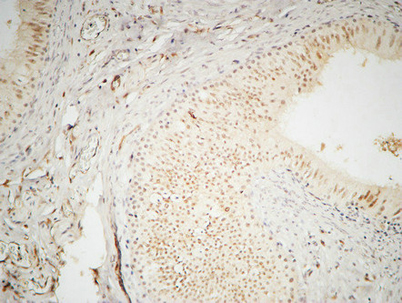

Product name: hnRNP A2/B1 rabbit pAb

Dilutions: Western Blot: 1/500 - 1/2000. Immunohistochemistry: 1/100 - 1/300. Immunofluorescence: 1/200 - 1/1000. ELISA: 1/20000. Not yet tested in other applications.